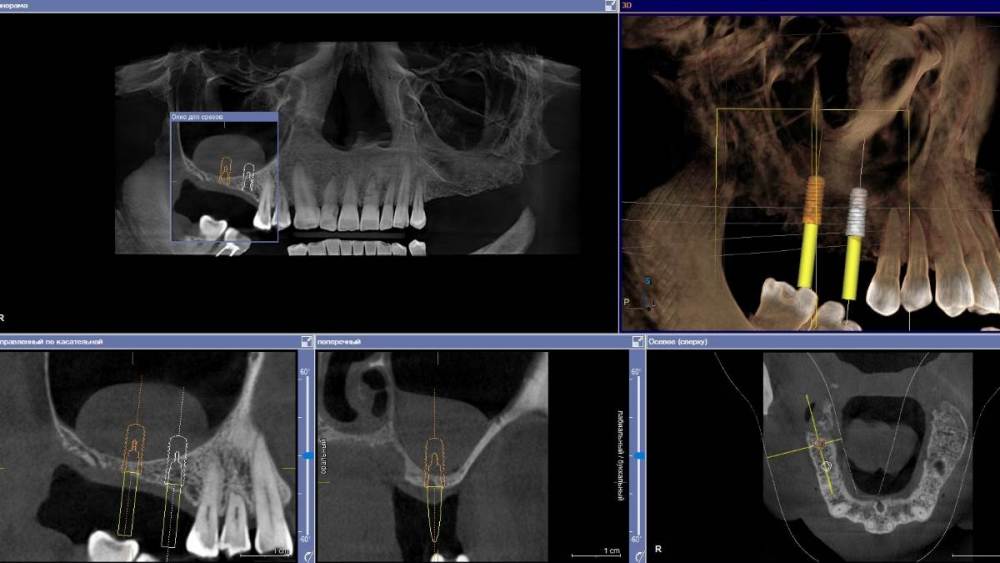

Ponchik Опубликовано 10 октября, 2021 Автор Поделиться Опубликовано 10 октября, 2021 16 часов назад, pit сказал: Составить полноценный план протезирования. План такой - 46,47 удаление. ОСЛ с двух сторон. Два импланта (на нижней челюсти справа 3) на каждую сторону и протезирование. В реальности - создал окно, в том месте где ожидал кисту пунктировал, но попадал в просвет пазухи (когда промывал физраствором, он тёк в глотку) в итоге место двух пробных пункций (и даже разреза на 2-3мм) закрыл мембраной и добавил графта. На кт потом увидел куда убежала киста. Теперь будем посмотреть. Ссылка на комментарий

Ponchik Опубликовано 10 октября, 2021 Автор Поделиться Опубликовано 10 октября, 2021 30 минут назад, Женька сказал: @Ponchik Ядах в своих вебах говорил, что главное чтобы отток через естественное соустье не закупорился... и всё тип топ будет. Что за кнопки? Мембраной закрыли ещё окно? Там соустье очень широкое. Если это единственное критичное место, то всё будет ок. 30 минут назад, Женька сказал: Что за кнопки? Мембраной закрыли ещё окно? Резорбируемая мембрана и пины по типу мейзингеровских. Бортик в стенке наружной не высокий вышел. Окно не маленькое. Да и графта 6(1.5*4) сс вышло. Вот и решил мембраной закрыть и на авось не надеятся. А то высыпалось однажды, правда там удачно вышло - и синус и по горизонтали прибавилось ))) 32 минуты назад, Женька сказал: Ядах в своих вебах говорил А у вас их есть? С переводом? Ссылка на комментарий

Ponchik Опубликовано 11 октября, 2021 Автор Поделиться Опубликовано 11 октября, 2021 9 часов назад, pit сказал: Почему все не сделали одномоментно? Синусы, удаления имплататы. Условия прекрасные! Удалил. Отправил к ЛОРу. Пациент пропал на 2 года. Потом оказалось, что просто финансово не тянет. Сделал синус справа - корейская мембрана и 4 биооса, месячная зарплата пациента, но ему помогает семья и они на вторую сторону через месяц, два наберут. Люди хорошие, решил помочь, за работу не беру. Авось не огребу от начальства. Но всё сразу делать они не могут даже если оплачивать только материалы. Ссылка на комментарий